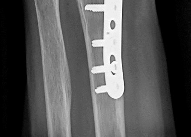

Question 7:

A 45-year-old trauma patient sustains an intra-articular distal femur fracture. Advanced imaging identifies a coronal plane fracture of the lateral femoral condyle (Hoffa fragment). Biomechanical studies suggest which of the following screw orientations provides the most rigid fixation for this specific fracture pattern?

Correct Answer: Posteroanterior oriented lag screws

Explanation:

A Hoffa fracture is a coronal plane fracture of the femoral condyle, more commonly affecting the lateral condyle. Biomechanical studies have demonstrated that posteroanterior (PA) directed lag screws provide superior stability and higher load to failure compared to anteroposterior (AP) directed screws. While AP screws are often used clinically due to ease of placement via an anterior approach, PA screws are biomechanically advantageous because they enter through thicker cortical bone posteriorly and are directed perpendicular to the fracture plane.